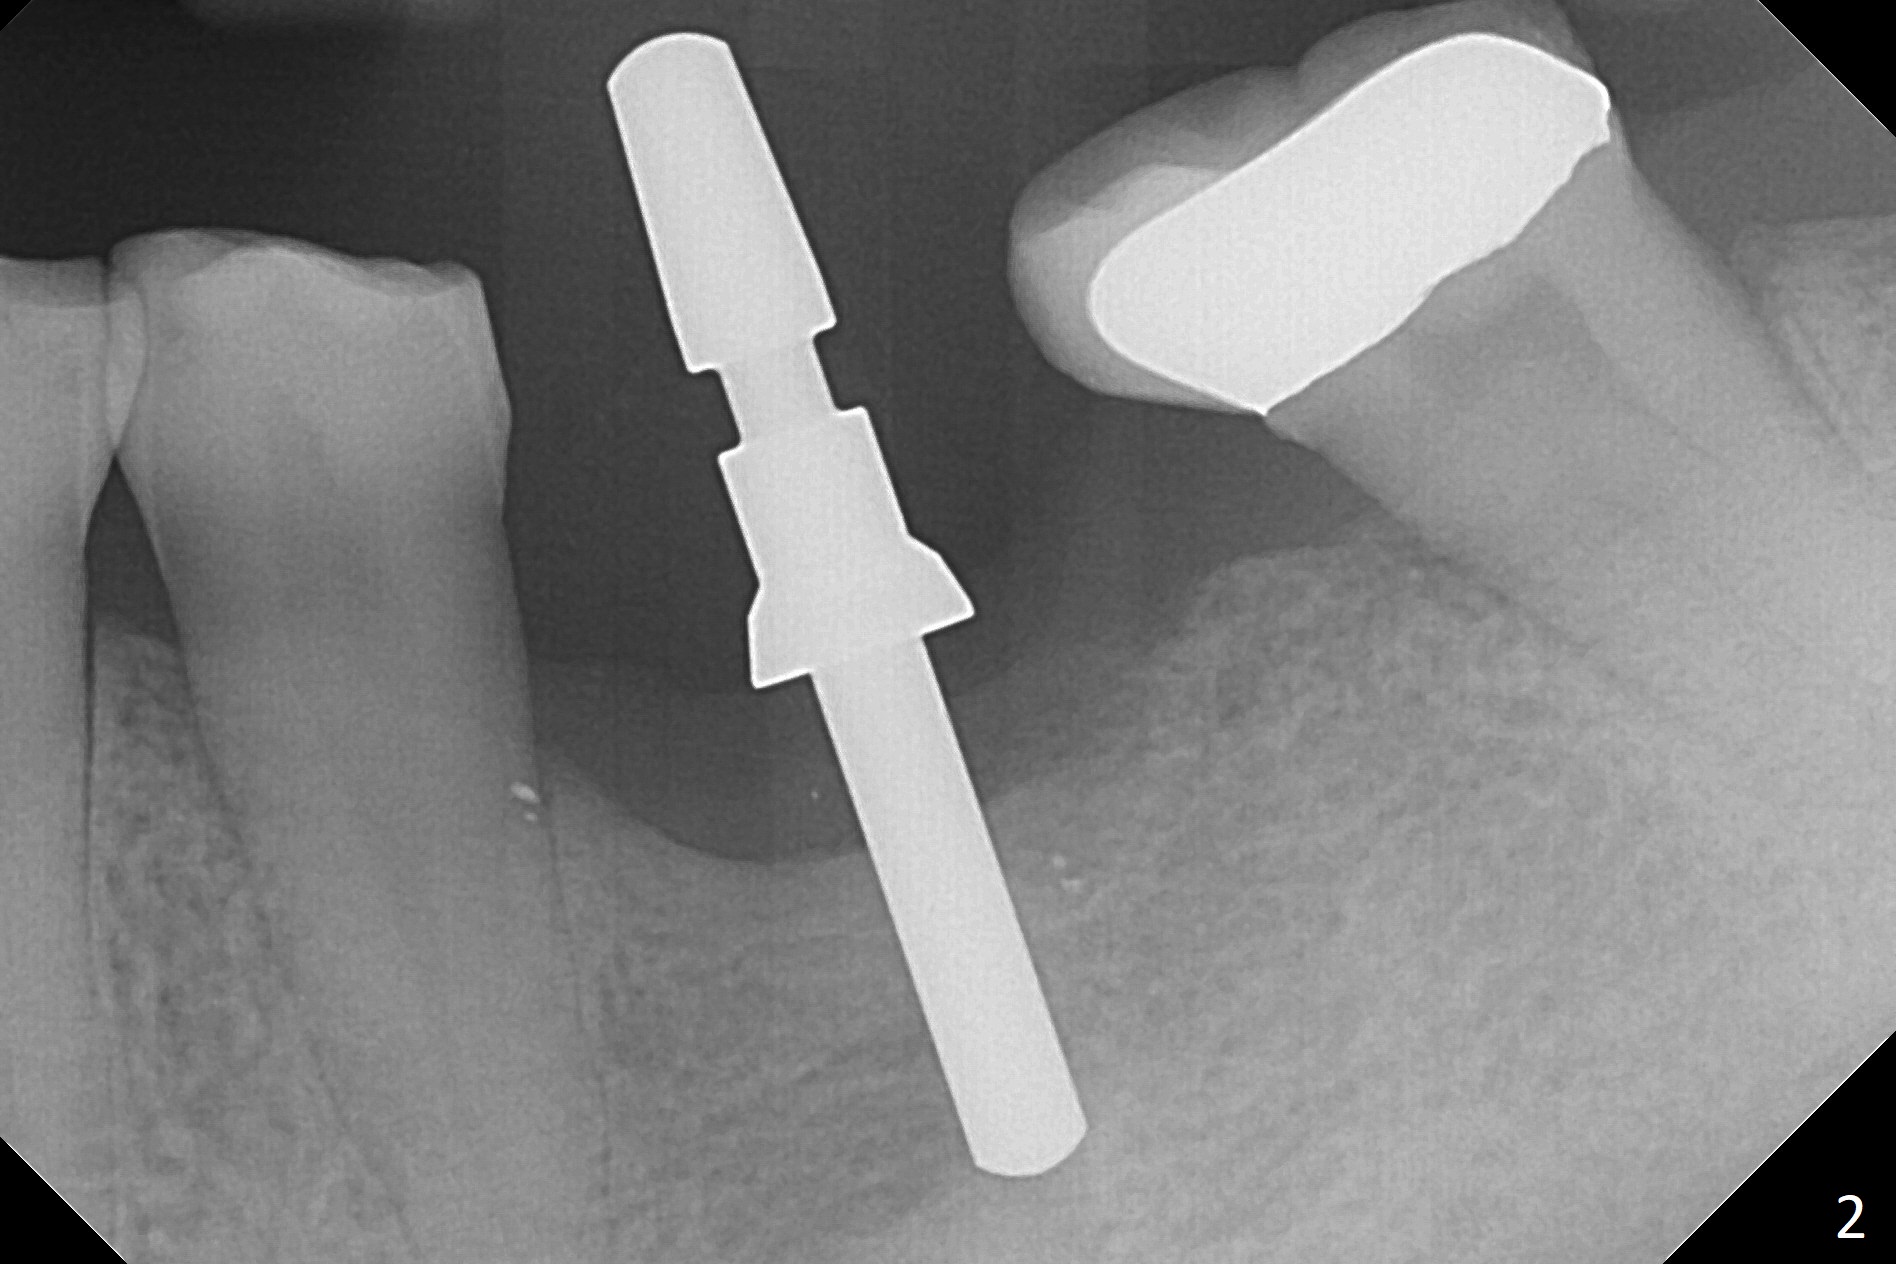

After extraction of the distal residual root at #19 (Fig.1), osteotomy is initiated in the mesial (M) aspect of the distal socket (Fig.2). Magic Split proves dense bone. When a 4.5x10 mm dummy implant is placed with stability, there is an apical space (Fig.3 <); the dummy abutment is 5.7x5.5(2). With the final implant (4.5x10 mm, Fig.4) being placed deeper to close the apical space, the cuff of the final abutment increases by 1 mm. Autogenous bone is used to pack around the implant distobuccally (*). Although the implant seems to be placed significantly apical to the lingual crest (^), it is at the buccal crest. There seems to be no bone loss 3 months postop; impression is taken (Fig.5). The crown/abutment at #30 is retightened 22 days post cementation (5 months postop), probably related to unilateral mastication. In fact, #30 is the only functioning molar on the right side (with unfavorable crown/implant ratio (long cuff 4 mm, vs. 3 mm at #19); #2 severely decayed); the crown at #19 is cemented at the same appointment (Fig.6). The crowns/abutments at #19 and 30 are loose 7 months later. When the crown/abutment at #30 is loose 2nd time 1 year 7 months post cementation, the screw at #19 fractures (Fig.7 taken post retightening). The tooth #2 needs a crown. The patient cannot use the anterior teeth, since the teeth #8 and 9 have root fracture. Can extraction and bone graft increase bone height? The abutment remains incompletely seated 9 months post screw replacement. It should be fixed soon. Return to Lower Molar Immediate Implant, Prevent Molar Periimplantitis (Protocols, Table), Armaments Screw Xin Wei, DDS, PhD, MS 1st edition 12/22/2017, last revision 02/24/2021